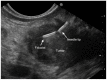

Pancreatic neuroendocrine neoplasms (PanNENs) are relatively rare, but their incidence has increased significantly in the last decades. Precise diagnosis and prognostic stratification are crucial for proper patient management. Endoscopic ultrasound (EUS) is the modality of choice for diagnosis of solid pancreatic tumors, showing a higher tumor detection rate than other imaging modalities, especially for small size lesions. EUS also serves as a guide for preoperative sampling and other interventions. EUS-tissue acquisition is a safe and highly accurate technique for cyto/histological diagnosis of PanNENs with a well-demonstrated correlation between Ki-67 proliferation index values and tumor grading on EUS and surgical specimens according to the WHO 2017 classification. Furthermore, the possibility of a preoperative EUS-guided fine needle tattooing or fiducial markers placement may help the surgeon to locate small and deep tumors, thus avoiding formal pancreatic resections in favor of parenchymal-sparing surgery. Finally, locoregional ablative treatments using either ethanol injection or radiofrequency ablation have been proposed in recent studies with promising results in order to control symptoms or reduce tumor burden in selected patients unfit for surgery with functioning or non-functioning PanNENs. This article review highlights the current role of EUS in PanNENs management, focusing on the present and future applications of EUS-guided interventions.